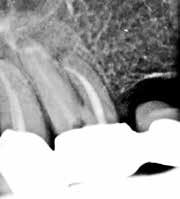

Fig. 1. A. Udsnit af panoramaoptagelse viser Ca(OH)2 uden for foramen apicale i en overkæbemolar og i sinus maxillaris (pil). B. Periapikal optagelse viser Ca(OH)2 uden for foramen apicale (pil) i en central incisiv. Tilfældet krævede kirurgisk indgreb.

Fig. 1 A. An orthopantomography section showing Ca(OH)2 beyond the apical foramen of maxillary first into the maxillary sinus (arrow) and (B) a periapical radiograph with Ca(OH)2 extrusion beyond the apical foramen (arrow) of a central incisor which required surgical intervention.

Ved mistanke om malpraksis vurderer man behandlerens handlinger i alle stadier i relation til opgavens kompleksitet og tager stilling til, om disse lever op til normen for almindelig anerkendt faglig standard. De mest omfattende skadevirkninger ses i forbindelse med anvendelse af endodontiske skyllevæsker og andre medikamenter, fx ulykker med natriumhypoklorit eller skader på nervevæv eller i sinus som følge af udpresning af calciumhydroxid igennem foramen apicale (Fig. 1A og B) (5,6). Sådanne uheld vurderes ofte til at være undgåelige, idet tandlægen ikke har levet op til normal faglig standard. Frygt for at begå procedurefejl eller andre utilsigtede hændelser bør dog ikke få klinikeren til helt at afstå fra at foretage endodontiske behandlinger (7).